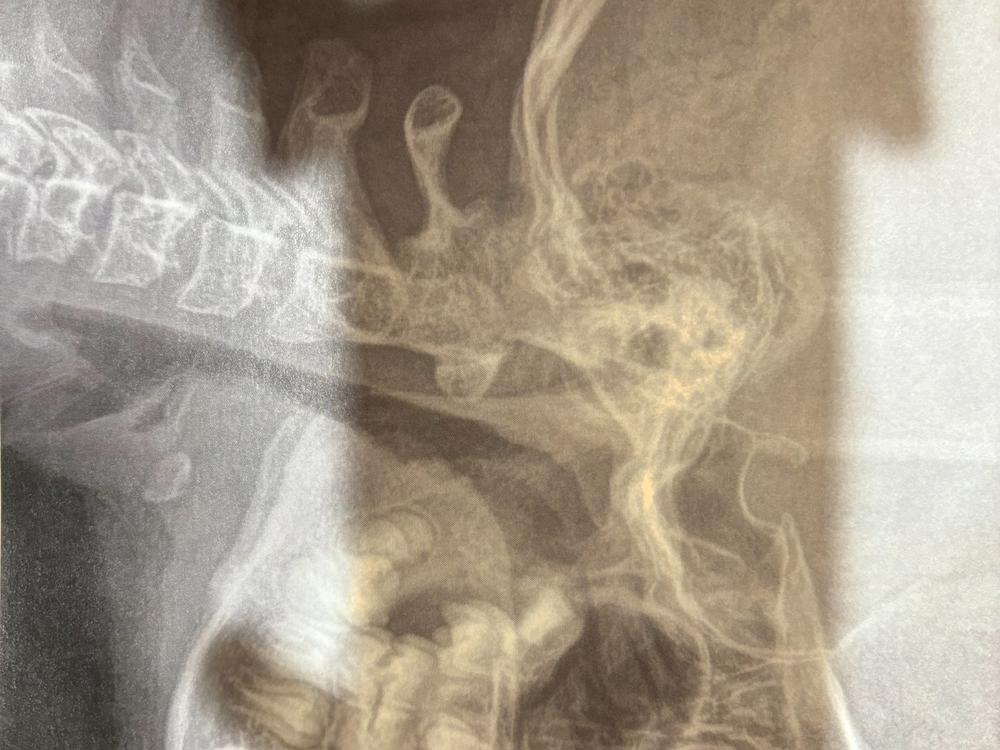

Hey famz, my 11 year old daughter Sophie is needing extensive dental treatment which includes a jaw expander followed by braces and then retainers throughout her life. Unfortunately, her dental needs/requirements are not free as she is under specialized care.

Without these treatments, not only are her teeth crooked which impacts on her mental health, her jaw is also affecting the shape of her face and compromising her airway.